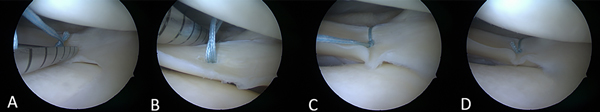

Se resolvió por medio de sutura meniscal todo-adentro (Meniscal Cynch™, Arthrex, EE. UU.) y suturas afuera-adentro asociadas según la extensión de la lesión meniscocapsular (figs. 2 y 3). Al año de la cirugía los pacientes fueron citados para poder realizarles examen físico y completar las escalas de Lysholm y Tegner para la reinserción deportiva. En la Tabla 1 se muestran las características demográficas de los pacientes destacando episodios de bloqueos y técnica quirúrgica utilizada en cada caso.

Figura 2: Rodilla izquierda. Secuencia de reparación con sistema todo-adentro, colocación del primer Meniscal Cynch™. A) Disparo de la primera sutura tomando el cuerpo meniscal. B) Disparo de la segunda sutura en la cápsula posterosuperior justo por detrás del ojal del poplíteo. C) Deslizamiento del nudo bajando y cerrando la sutura. D) Configuración vertical de la reparación meniscal.

Las cirugías fueron efectuadas por el mismo equipo quirúrgico (HR, CC, MM). En primer lugar, se realizó la artroscopía en la que se confirmó el diagnóstico de menisco externo hipermóvil por desinserción meniscocapsular posterior, con lesión de ligamentos meniscales (meniscos capsulares) posteriores, también se constató la calidad del menisco, tratando de buscar un patrón lesional artroscópico (ver fig. 3). Luego se cruentaron los bordes de la lesión y se realizó su reparación-sutura con sistema todo-adentro Meniscal Cynch™ (Arthrex, EE. UU.), y en algunos casos, a demanda, se combinó con técnica afuera-adentro, utilizando el remanente de la sutura meniscal todo-adentro Fiberwire® 2.0, con puntos verticales. Posteriormente a la fijación meniscal se verificó su estabilidad utilizando el palpador, con movimientos de flexión y extensión bajo control artroscópico. En todos los casos se constató un menisco firme y estable (figs. 4 y 5).

Figura 4: Rodilla izquierda. Reparación con sistema todo-adentro Meniscal Cynch™. A) Primer Meniscal Cynch™ cerca de la inserción posterior del menisco externo tomando cápsula posterosuperior y cuerpo meniscal. B) Segundo y tercero Meniscal Cynch™ tomando la cápsula posterosuperior justo por detrás del ojal del poplíteo. C) Visión del tercer punto por detrás y cuarto punto por delante del tendón del poplíteo. D) Cuarto Meniscal Cynch™, pretendón del poplíteo. Configuración vertical de la reparación meniscal.